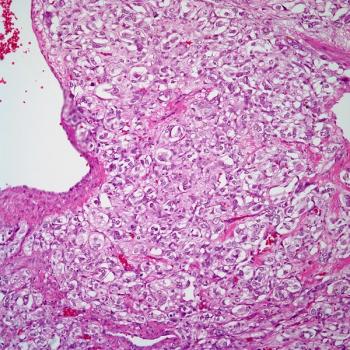

A 41-year-old woman presents with a palpable mass in her left breast. A lumpectomy is performed. What is your diagnosis?